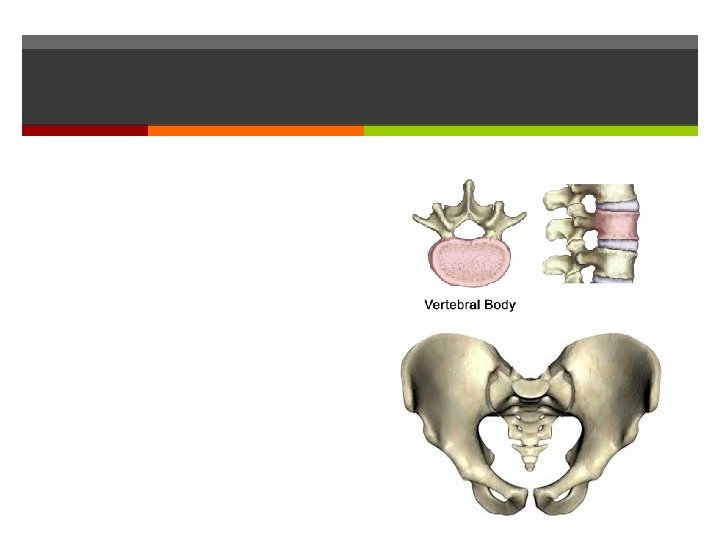

Fractures

Fractures Treated by Reduction: Closed Open